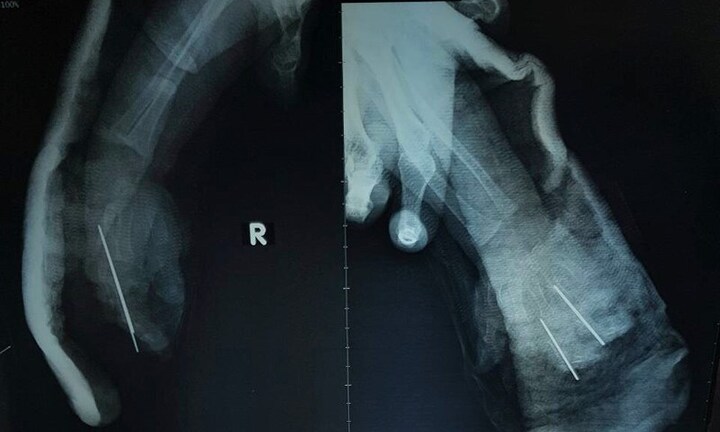

Trong quá trình lao động bàn tay trái bị cuốn vào máy nghiền gây vết thương phức tạp, đã băng ép cầm máu và được gia đình đưa vào viện cấp cứu.